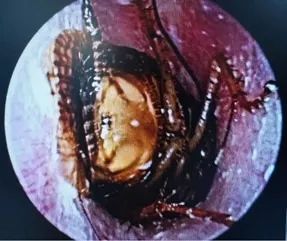

图1 耳内镜所见:外耳道内被异物占据。

今天在门诊遇到一位85岁老人,因左耳堵塞感就诊,自己以为是耳屎堵了。于是给她拍个耳内镜一看,这图片应该是异物啊?!老人说不清楚,只说平时佩戴助听器。她从口袋里拿出她的助听器给我们看过以后,便清楚,这个东西可能是她助听器上的耳塞。用异物钳取出来一看,果然是耳塞掉进去了,而且时间还很长了,硅胶耳塞已经有点氧化变色了。